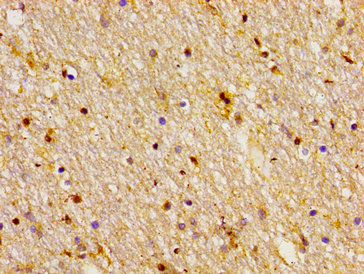

Immunohistochemistry of paraffin-embedded human brain tissue using CSB-PA891782LA01HU at dilution of 1:100